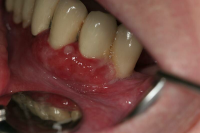

Akut, lokalt begränsad purulent (varig) inflammation i tandens parodontala vävnader.

Den vanligaste orsaken är akutisering av en kronisk parodontit som är associerad med en djup tandköttsficka eller en furkationsinvolverad tand.

Svullnad, rodnad och ömhet, ibland värk.